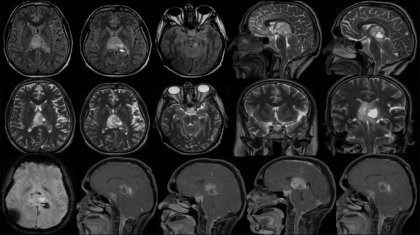

35 yr old male c/o headache, quadriparesis and blurring of vision.